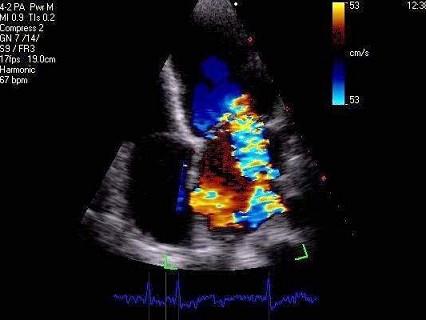

问题 风心病最易累及的部位是?(?)

选项 A.二尖瓣 B.三尖瓣 C.主动脉瓣 D.肺动脉瓣 E.以上均是

答案 A